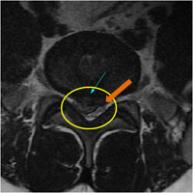

MRI

MRI ġ